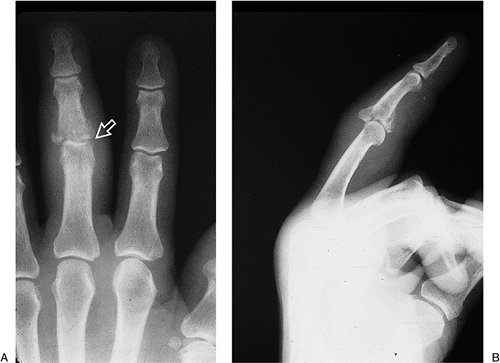

Figure 9-8 demonstrates the x-ray appearance of such an injury.

Figure 9-8 X-ray appearance of a comminuted and displaced fracture subluxation of the base of the middle phalanx. -

An example of a similar injury in the

traction to treat such an injury (Figure 9-9).-

These first two examples are contrasted to an unstable fracture-dislocation of the PIP joint with a relative large and non-comminuted fragment that can be reduced and fixed.

Such an anatomic reduction is stable and with early protected motion, an excellent outcome may be anticipated (Figure 9-10).

Figure 9-9 A dynamic traction method for treatment of a comminuted and displaced fracture of the proximal phalanx of the thumb. A, B. Pretreatment x-ray appearance; note the comminution and volar subluxation of the proximal phalanx. C.

Figure 9-10 A noncomminuted but unstable volar lip fracture-dislocation of the base of the proximal phalanx that is amenable to fixation. -